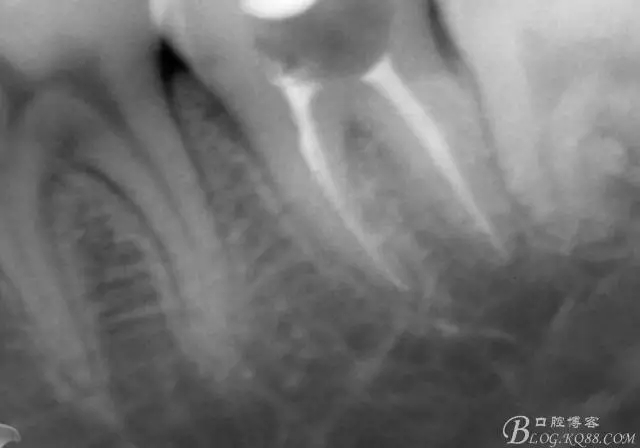

X線示牙膠尖到達工作長度,故行AH-PLUSH糊劑配合卡瓦熱牙膠機運用連續(xù)波充法根充,暫封拍根尖片。

第四次復診,37叩(—)。此次行冠部修復,因涉及38的拔除,患者不愿拔除,與患者介紹修復材料與方法,擬37E.max嵌體修復,術前常規(guī)簽修復知情同意書。